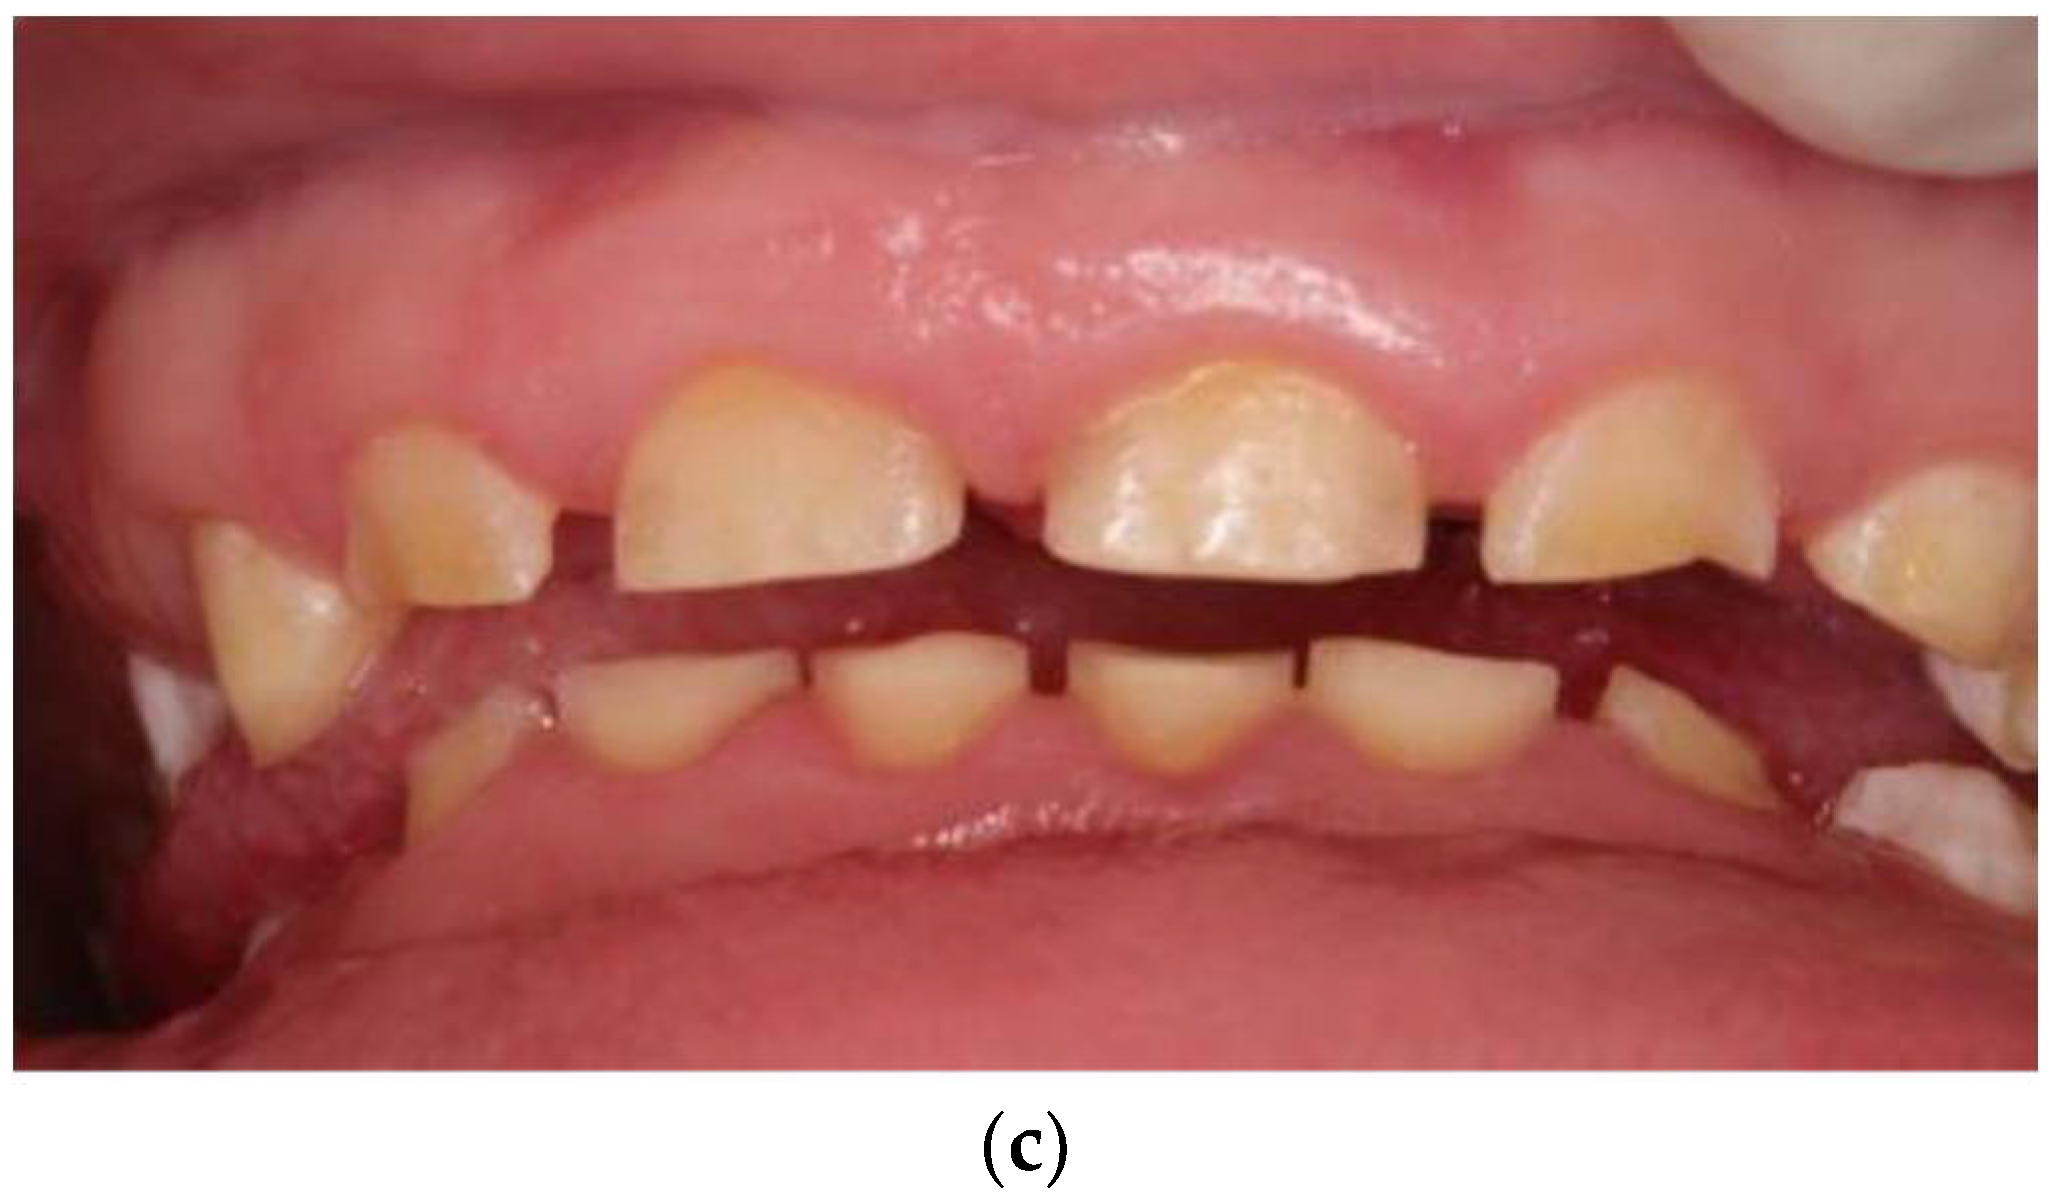

2.2. Case Report: Permanent Dentition